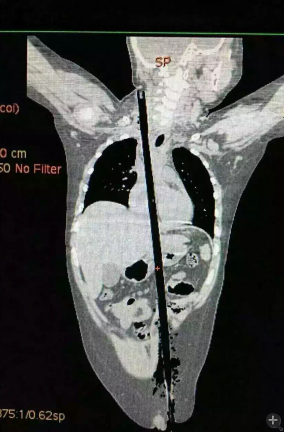

據(jù)相關(guān)知情人介紹,受傷男童24日晚在家中與小朋友一塊兒在墻頭上玩耍時(shí),一不小心從高墻上跌落到了鄰家花圃中,讓人觸目驚心的是,該男童正好跌到了花圃中的一支長(zhǎng)約63厘米,直徑約1.5厘米的竹棍上,竹棍自孩子的左側(cè)大腿根部直接插入腹腔并入胸腔直至右側(cè)頸部。

市兒童醫(yī)院組織專家團(tuán)隊(duì)對(duì)孩子的病情進(jìn)行檢查、評(píng)估后發(fā)現(xiàn),竹棍由患兒左側(cè)大腿根部插入,經(jīng)腹腔穿透胃、肝臟、膈肌入胸腔,并穿透患兒心臟,經(jīng)胸腔入頸部,此刻不能拔除竹棍,因?yàn)槿コ窆鲿?huì)導(dǎo)致心臟、肝臟破裂大出血導(dǎo)致休克,危及性命。

由于竹棍自心臟的右心房膈面穿入心臟,并由右房近左房頂處穿出心臟,經(jīng)右胸頂刺入右頸部,右心房破口處緊鄰右冠狀動(dòng)脈,幸運(yùn)的是胸腔內(nèi)大血管無(wú)損傷,在體外循環(huán)輔助下,醫(yī)護(hù)團(tuán)隊(duì)異物穿出處鋸斷異物,將插入心臟內(nèi)的竹棍截?cái)喟纬,修補(bǔ)心臟破損處,向上繼續(xù)尋找周圍組織的游離異物,見(jiàn)異物緊臨頸部大血管,經(jīng)精細(xì)手術(shù),終于抽出了異物。整個(gè)手術(shù)時(shí)間花了十多個(gè)小時(shí)。